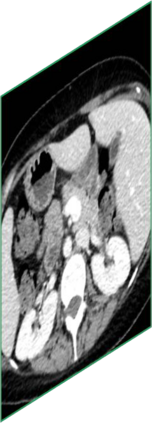

Due to the constraints of the imaging device and high cost in operation time, computer tomography (CT) scans are usually acquired with low intra-slice resolution. Improving the intra-slice resolution is beneficial to the disease diagnosis for both human experts and computer-aided systems. To this end, this paper builds a novel medical slice synthesis to increase the between-slice resolution. Considering that the ground-truth intermediate medical slices are always absent in clinical practice, we introduce the incremental cross-view mutual distillation strategy to accomplish this task in the self-supervised learning manner. Specifically, we model this problem from three different views: slice-wise interpolation from axial view and pixel-wise interpolation from coronal and sagittal views. Under this circumstance, the models learned from different views can distill valuable knowledge to guide the learning processes of each other. We can repeat this process to make the models synthesize intermediate slice data with increasing inter-slice resolution. To demonstrate the effectiveness of the proposed approach, we conduct comprehensive experiments on a large-scale CT dataset. Quantitative and qualitative comparison results show that our method outperforms state-of-the-art algorithms by clear margins.